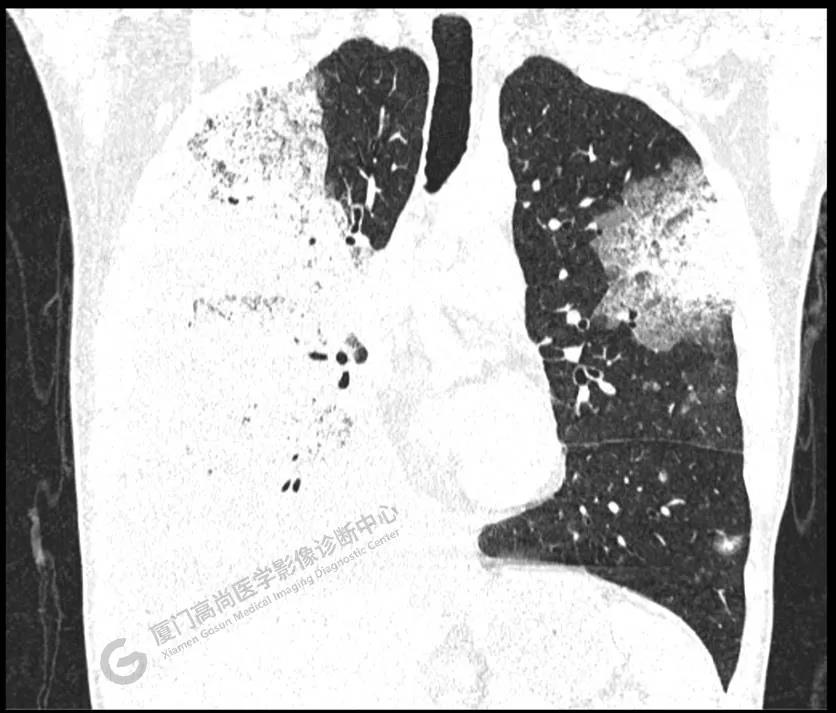

PET/CT影像圖

圖2

PET/CT所見(jiàn):雙肺大片實(shí)變影及磨玻璃影,部分呈地圖樣改變,累及右肺尖,部分放射性攝取輕微增高,SUVmax 1.77,其內(nèi)見(jiàn)多發(fā)支氣管充氣征象。

影像診斷: 雙肺大片實(shí)變影及磨玻璃影,大部分代謝不高,局部代謝輕微增高,考慮肺泡蛋白沉積癥,建議病理學(xué)檢查或肺泡灌洗物檢查。

影像學(xué)表現(xiàn):HRCT上雙肺斑片影,以肺門為中心呈蝶翼狀對(duì)稱分布;病變可隨機(jī)分布在中央?yún)^(qū)、周圍區(qū)或全肺葉,病灶與正常分組織分界清楚,呈典型“地圖樣”改變;有支氣管充氣征,但表現(xiàn)為充氣支氣管細(xì)小且數(shù)量及分布稀少;“碎石路”征由彌漫性磨玻璃影及內(nèi)部網(wǎng)格樣小葉間隔增厚組成(鋪路石樣表現(xiàn))。無(wú)空洞、蜂窩狀改變、淋巴結(jié)腫大、胸腔積液及明顯實(shí)變等。肺內(nèi)病灶累及范圍、磨玻璃密度高低與PAP患者的病情嚴(yán)重程度相關(guān),嚴(yán)重者病灶累及全肺,同時(shí)出現(xiàn)肺內(nèi)大片實(shí)變,并見(jiàn)充氣支氣管征象。PAP影像學(xué)表現(xiàn)程度與臨床癥狀、體征嚴(yán)重程度不成比例,表現(xiàn)為影像改變重,臨床癥狀輕。